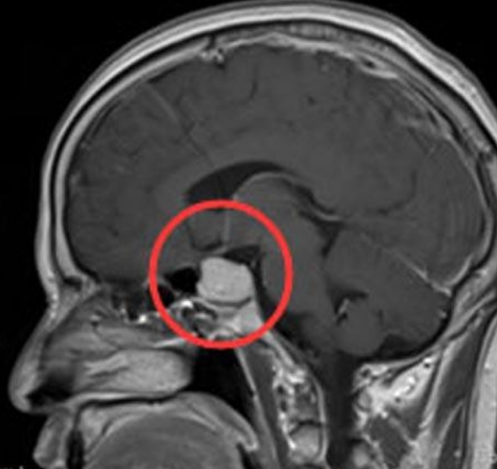

什么是垂体瘤 ,该怎么做才能切除? 垂体瘤是垂体内可见的异常生长。在大多数情况下,这些肿瘤是良性的。有一些垂体瘤会使垂体分泌异常高水平的激素,这可能导致荷尔蒙失调,...